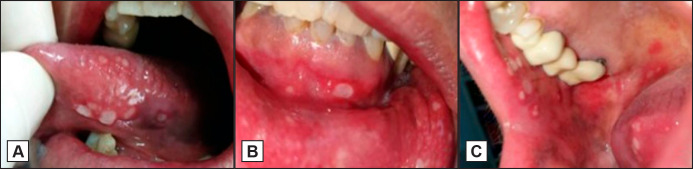

Results: Clinical examination revealed multiple aphthous-like ulcers on the ventral surface and lateral borders of the tongue, lower lip and mucolabial fold, buccal mucosa and soft palate. Dexamethasone oral solution 0.5 mg/5 ml was topically administered t.i.d. along with tramadol 50 mg per os t.i.d. for pain management. One week later, the pain was relieved and the ulcers were almost completely healed. Tramadol administration was discontinued and dexamethasone was tapered during the following 8 days. There was no need for discontinuation of panitumumab. In close follow-up for the next four months, no painful oral symptomatology was reported.